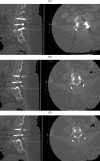

Figure 6

(A) Postoperative sagittal and axial computed tomography (CT) spine at L2 pedicle. (B) Postoperative sagittal and axial CT spine at L3 pedicle. (C–E) Postoperative sagittal and axial CT spine at L4 pedicle. Axial image showing the amount of tumor that was resected including the medial wall of the left L3 pedicle.

Continued.